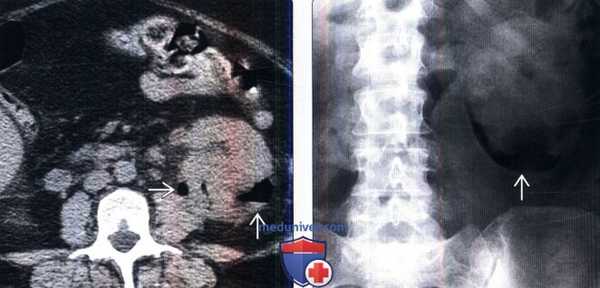

(Левый) При КТ без контрастирования у этого пациента визуализируется хроническая обструкция и инфекция в левой почке, осложнившиеся значительным истончением коркового вещества с замещением лоханки и паренхимы почки скоплениями газа и жидкости .

(Правый) На аксиальном КТ срезе у другого пациента с эмфизематозным пиелонефритом визуализируется ограниченное скопление газа в паренхиме верхнего полюса левой почки. Обратите внимание на окружающие воспалительные изменения, указывающие на хроническую инфекцию. (Левый) На фронтальном КТ срезе у этого же пациента вновь визуализируется незначительное скопление газа в паренхиме. Обратите внимание на другие признаки инфекции: значительное увеличение левой почки, кортикальный абсцесс, утолщение уротелия почечной лоханки и отсроченное контрастирование на нефрограмме.

(Правый) На более нижнем аксиальном КТ срезе у того же пациента визуализируются скопления газа в толстостенных очагах обеих поясничных мышц , в результате осложнения эмфизематозного пиелонефрита. (Левый) На аксиальном Т1-ВИ в отсроченную фазу у этого же пациента на том же исследуемом уровне визуализируются двусторонние абсцессы поясничных мышц.

(Правый) На продольном Т2-ВИ у этого же пациента визуализируется патологический высокоинтенсивный сигнал в прилежащем теле позвонка L4, указывающий на развивающийся остеомиелит. У этого пациента с сахарным диабетом, эмфизематозным пиелонефритом, абсцессами поясничных мышц и остеомиелитом позвоночника имеются картина сепсиса и сильные боли в спине..

(Слева) КТ без контрастирования, аксиальная проекция: у женщины 69 лет с сахарным диабетом, поступившей с лихорадкой и болью в боку, выявлены крупные скопления газа и жидкости в паренхиме почки слева. Такая картина характерна для абсцесса, продуцирующего газ, сформировавшегося вследствие наличия эмфизематозного пиелонефрита.

(Справа) Рентгенография в переднезадней проекции: у этой же пациентки имеется нелинейное скопление газа , очерчивающее нижний полюс левой почки.